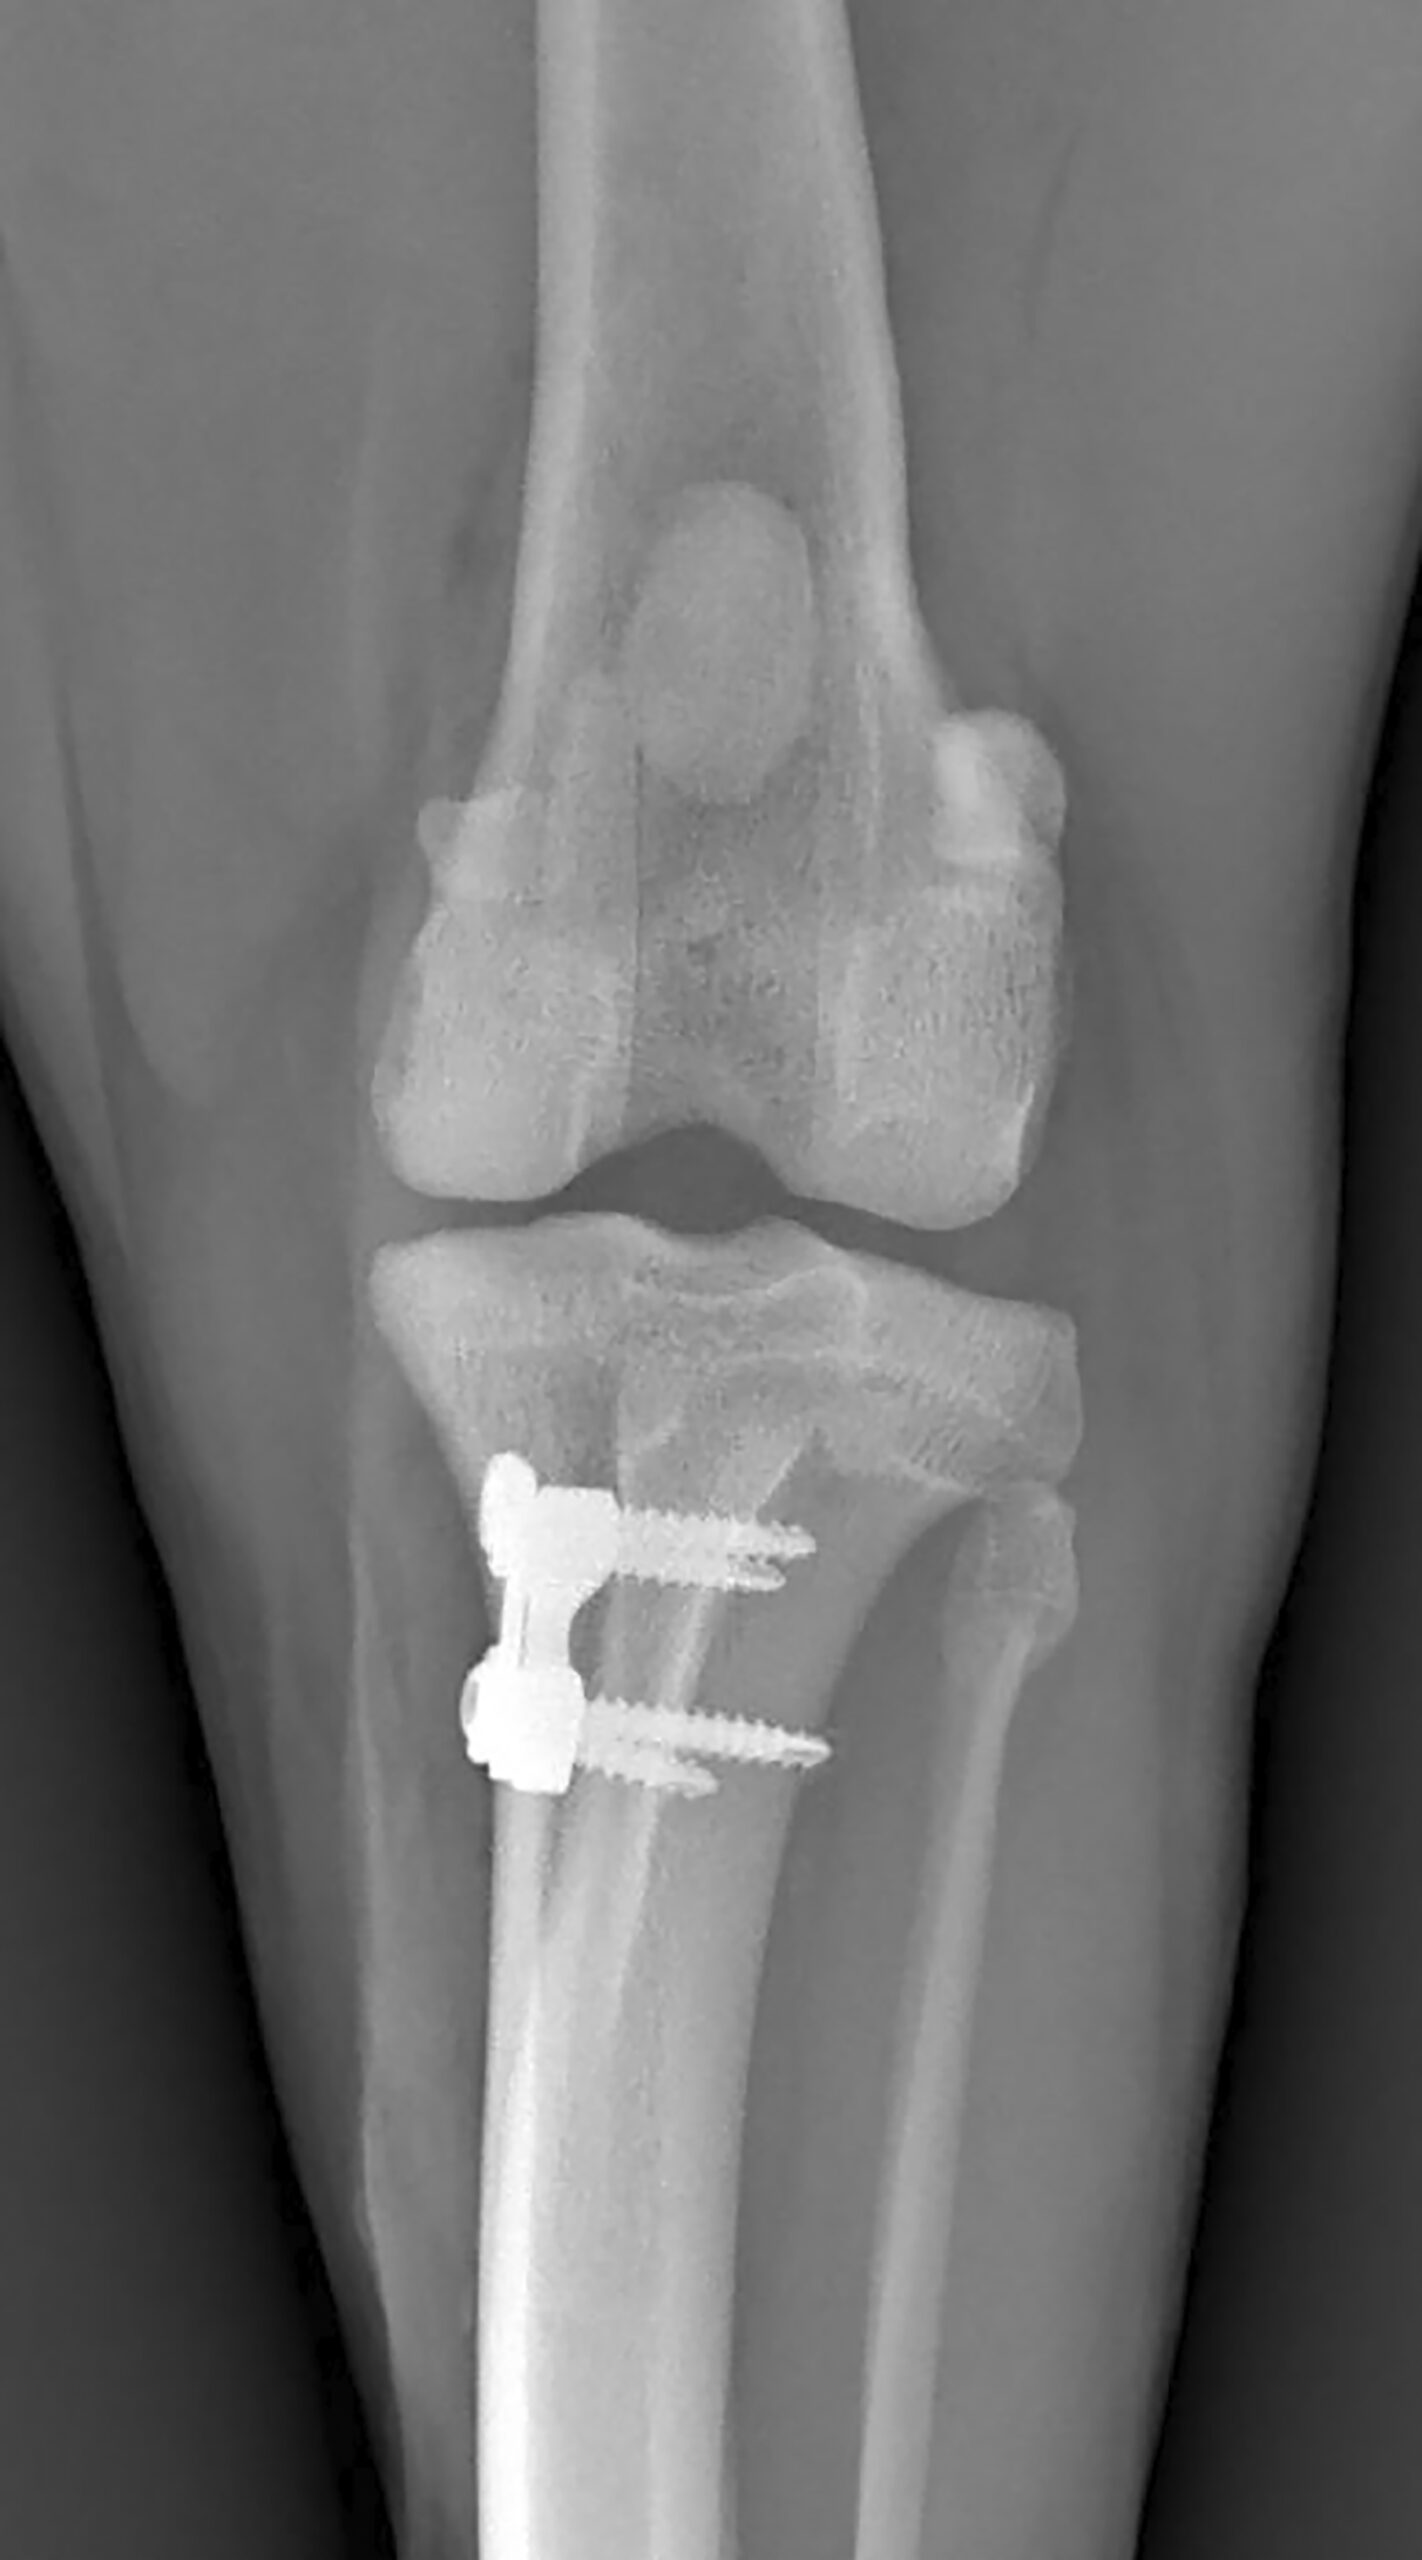

As a Tibial Tuberosity Transposition (TTT) Technique, the RAPID Patella Luxation Technique offers an enhanced procedure through its uniquely-designed RAPID Patella Plates and Spacers, as well as its specialized instrumentation, enabling a safe and precise correction of a patella luxation.

Taking inspiration from the success of TTA RAPID®, the RAPID LUXATION Plating System (RLPS) was developed specially for the correction of a patella luxation.

This study examined 37 cases that underwent surgical treatment for medial patellar luxation (MPL), utilizing Tibial Tuberosity Transposition (TTT) with the RAPID LUXATION Plating System (RLPS). The findings indicate that TTT using RLPS offers a viable technique across a broad spectrum of patients with MPL, reducing the incidence of implant-related complications as well as tibial tuberosity avulsion or fracture.